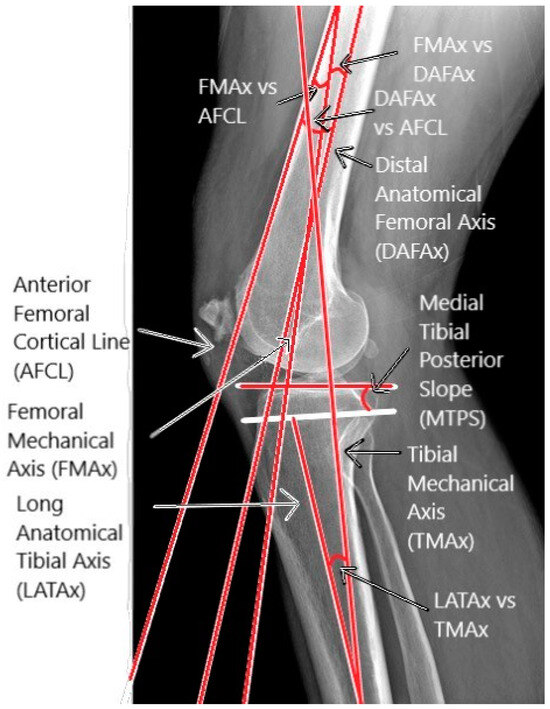

2.2. Sagittal Parameters